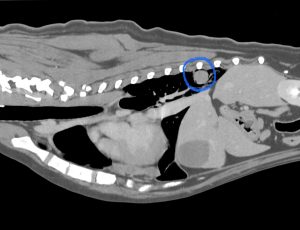

こんにちは。獣医師の永井です。 今回は肺葉捻転についてです。 犬猫の肺はバナナの房のように前葉、中葉、後葉(副…]]>

こんにちは。獣医師の永井です。 今回は肺葉捻転についてです。 犬猫の肺はバナナの房のように前葉、中葉、後葉(副…]]>